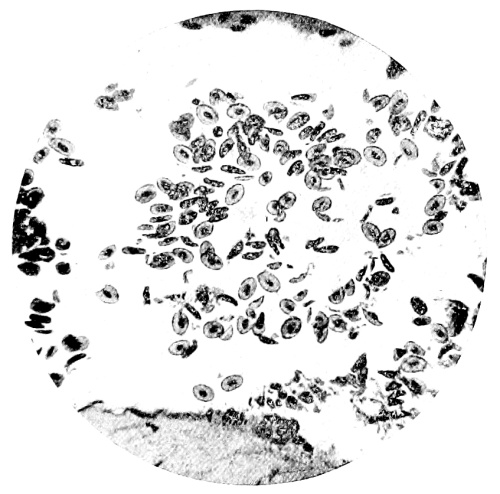

8. Measurement of Blood Corpuscles (human) 97

9. Measurement of Blood Corpuscles (sheep) 97

10. Photo-micrograph of Red Blood Corpuscles from Domestic Fowl 99

11. Photo-micrograph of Blood Corpuscles of Fish 99

12. Photo-micrograph of Blood Corpuscles from a Dried Stain of the Blood of a Cod-fish 100

13. Photo-micrograph of a Frog‘s Blood showing oval nucleated Red Corpuscles 101